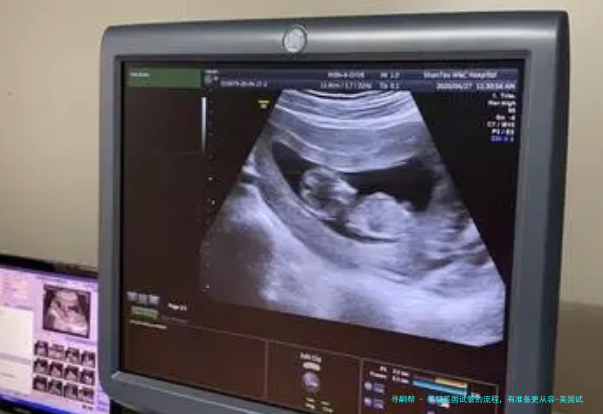

2、B超检查

第二次看诊的时间诊所护师会帮客人确认,按照护士的要求,定期进行B超检查、抽血检查以及卵泡监测,卵泡的监测一般在监测4-5次就能安排助孕。